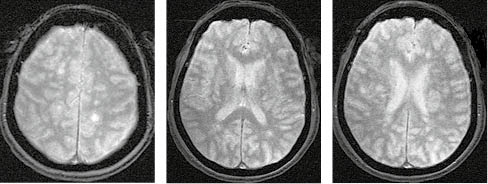

За МРТ-зображення головного мозку пацієнта з ГРЕМ у режимі Т2/Flair та Т1 із внутрішньовенним контрастуванням візуалізуються двобічні вогнища, гіперінтенсивні за Т2/Flair, які в переважно накопичують контраст і розташовані на рівні базальних ядер і таламусів, що є типовою клінічною ознакою ГРЕМ (рис. 2).

/images/nn257-1622023r2_.jpg)

У режимі Т2*/T2 GRE на МРТ-зображенні головного мозку пацієнта з ГРЕМ візуалізуються двобічні гіперінтенсивні вогнища без геморагічного компоненту, що є типовою ознакою ГРЕМ, на відміну від гострого геморагічного лейкоенцефаліту (хвороби Херста) (рис. 3).

/images/nn257-1622023r3_.jpg)